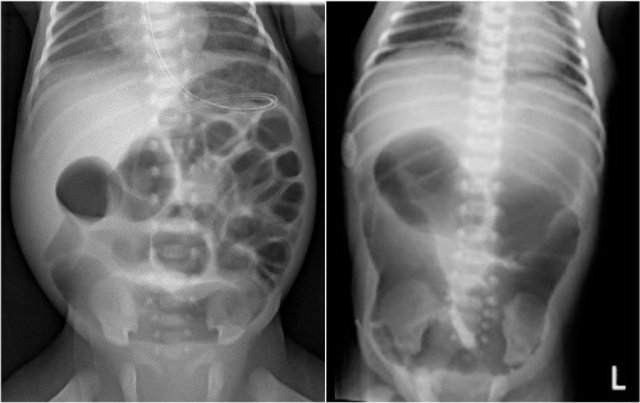

Case 2

Study the image.

What are the findings and what is your diagnosis.

Then scroll through the images for the diagnosis.

The findings are:

- Multiple dilated small bowel loops indicate a low obstruction

- Contrast enema show a small caliber of the rectum compared to the caliber of the sigmoid

- The rectum shows saw tooth contractions.

Diagnosis:

Short segment Hirschsprung disease.